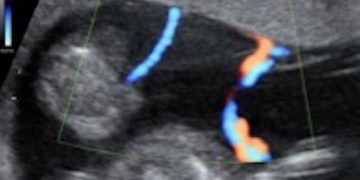

How To Do Settembre 2022: corretto settaggio del Doppler in ostetricia

Cari soci, questo mese un nuovo video "How to do", sul corretto settaggio del Doppler in Ostetricia. Grazie a Paola Quaresima! Il video è accessibile ai soli soci SIEOG attraverso...